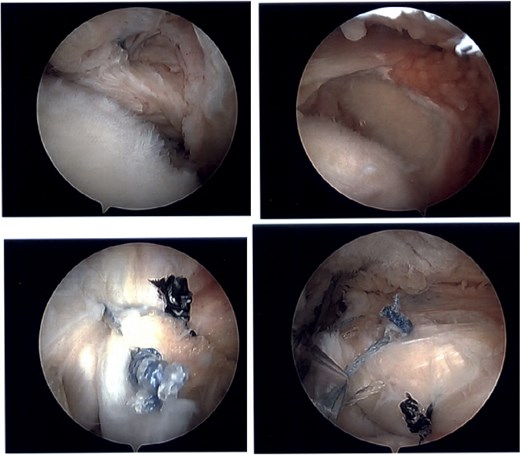

The patient continued to experience right shoulder disability, including pain, limited range of motion, and sleep disturbance. Operative intervention was delayed due to elevated liver enzymes, attributed to chronic acetaminophen use; he underwent right shoulder arthroscopy ~9 months after injury. Intraoperative findings confirmed extensive, irreparable tearing of the supraspinatus and infraspinatus, glenohumeral degenerative change, and deficient biceps tendon (Fig. 8). The joint was debrided and staged reverse total shoulder arthroplasty (rTSA) was discussed.

Intraoperative imaging of right shoulder arthroscopic debridement including findings of full-thickness supraspinatus and subscapularis tendon tears, which subsequently were not able to be repaired, as well as significant glenohumeral degenerative change.